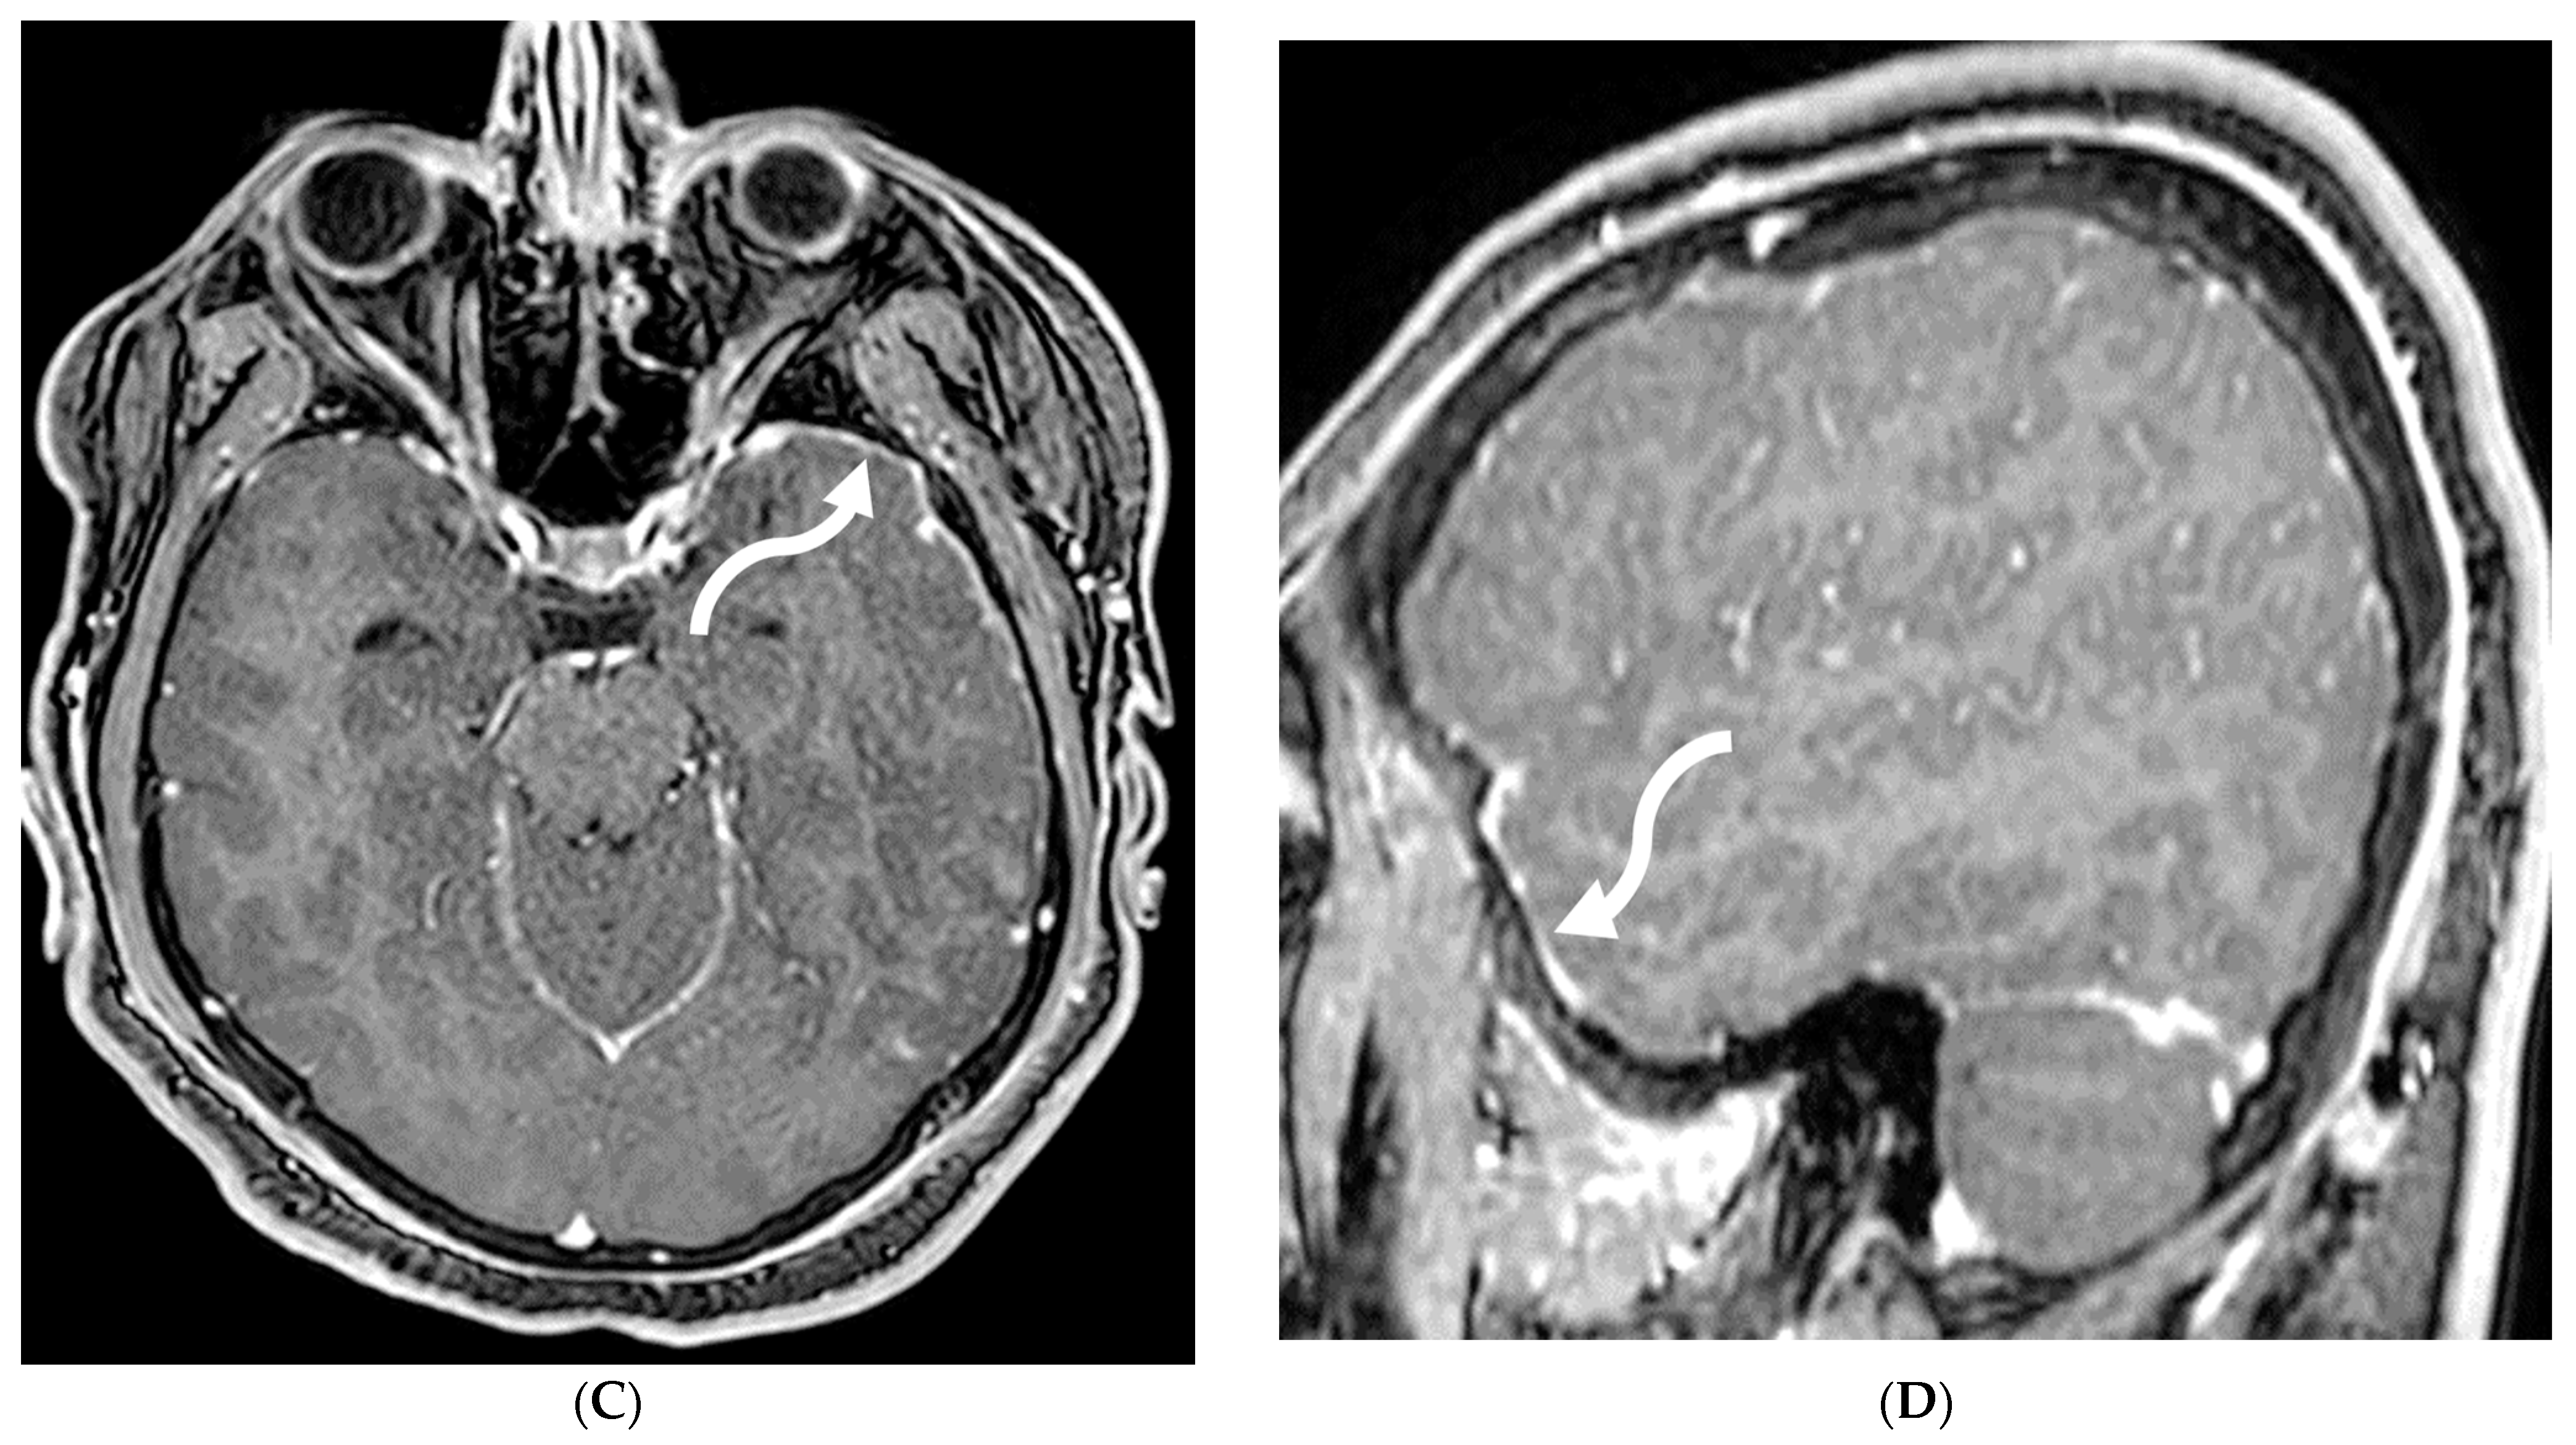

5.4. Granulomatosis Polyarteritis (GPA)

GPA is an autoimmune necrotizing granulomatous inflammation associated with anti-neutrophil cytoplasmic antibody (ANCA) vasculitis. This multisystem disorder predominantly affects small vessels, causing endothelial injury and tissue damage in the upper and lower respiratory tract and renal system [109,110]. Neurologic involvement occurs in 20–50% of GPA patients, mediated by three main mechanisms: vasculitis of cerebral vessels, granuloma formation due to contiguous involvement from adjacent paranasal and orbital lesions, and remote granulomatous lesions in brain parenchyma or meninges [111,112]. Patients typically present with headache, altered mental status, and transient ischemic attacks. Pituitary gland involvement can manifest as hyperprolactinemia or diabetes insipidus [111].

Imaging findings in GPA include chronic hypertrophic pachymeningitis (most common) representing granulomatous involvement. This can be diffuse or focal, with the latter showing dural thickening and enhancement adjacent to a sinus or orbit [113]. Tentorium involvement is common, presenting as the ‘Eiffel by night’ sign [114]. Cerebral vasculitis appears as multiple T2 hyperintense white matter lesions potentially showing diffusion restriction and patchy enhancement. Cerebral atrophy may be observed, attributed to steroid treatment and/or vasculitis. Pituitary involvement can range from normal to enlarged gland size, with thickened stalk and peripheral enhancement. Cranial nerve involvement, particularly of the olfactory and optic nerves, is common due to mass effect from adjacent lesions or hypertrophic pachymeningitis (Figure 22) [112].

Figure 22.

Post contrast axial FLAIR (A), axial T1 FS (B), sagittal T1 Right (C) and Left (D): 10-year-old girl with elevated ANCA, headache and mild LUE weakness. There is bilateral anterior temporal smooth dural enhancement (white arrows). Diagnosis: Antineutrophilic cytoplasmic antibody (ANCA) associated vasculitis, likely granulomatosis with polyangiitis.